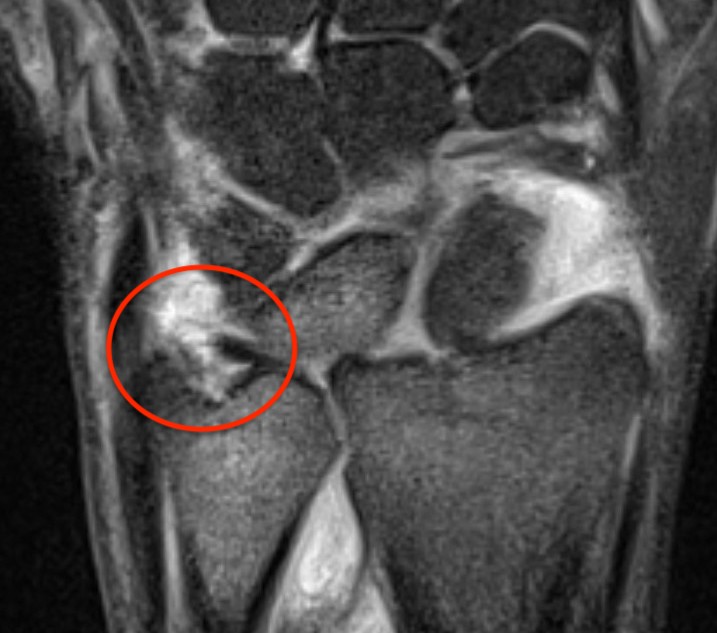

Ulno-carpal abutment

Ulnocarpal abutment and lunate chondromalacia

Ulna positive with ulnocarpal osteoarthritis

Class 2 Degenerative TFCC tears

Central TFCC tear with ulna positive variance an ulnocarpal abutment on MRI

Ulna impaction syndrome / Ulno-carpal abutment

Progression of wear

- TFCC thinning

- ulna head and lunate cartilage wear

- TFCC perforation

- lunate-triquetral ligament injury

- ulnocarpal osteoarthritis

Usually associated with ulna positive variance and treated with ulna shortening